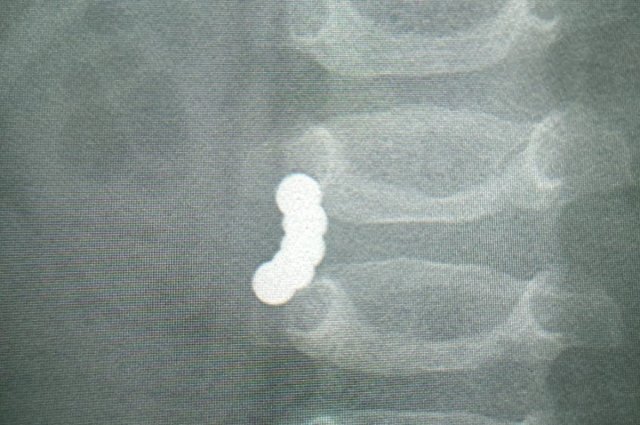

В Тобольске хирурги извлекли 23 магнитных шарика из желудка ребенка

Родители доставили ребенка в больницу. Он жаловался на боли в области живота. При проведении медицинского обследования было выявлено, что в брюшной полости пациента скопились инородные тела.

Особо опасным фактором оказались магниты, которые притянулись друг к другу и соединили органы между собой. Поэтому у пациента могла возникнуть непроходимость, а также грозило повреждение стенок кишечника и желудка.

По информации, полученной из больницы, врачи смогли удалить несколько металлических шариков методом гастроскопии. Однако доступ к определенному количеству примагниченных частей, которые сцепили органы между собой, возможен был только при помощи рассечения брюшной полости.

Хирургическая операция продолжалась около трех часов, в результате чего удалось извлечь все 23 магнита. В настоящее время жизни и здоровью ребенка ничего не угрожает.